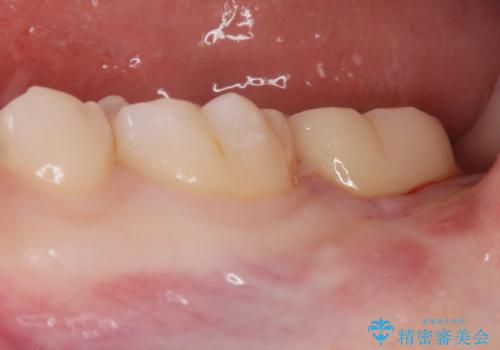

- 左下奥歯が痛いとの事で来院。

親知らずが炎症を起こしていたので抜歯をし、手前の歯は拡大鏡下で虫歯を取り除き、ジルコニアクラウンで治療をしました。

- ジルコニアクラウンスタンダード・仮歯 12.1万円 親知らず抜歯 保険適応費用は治療当時の料金となります